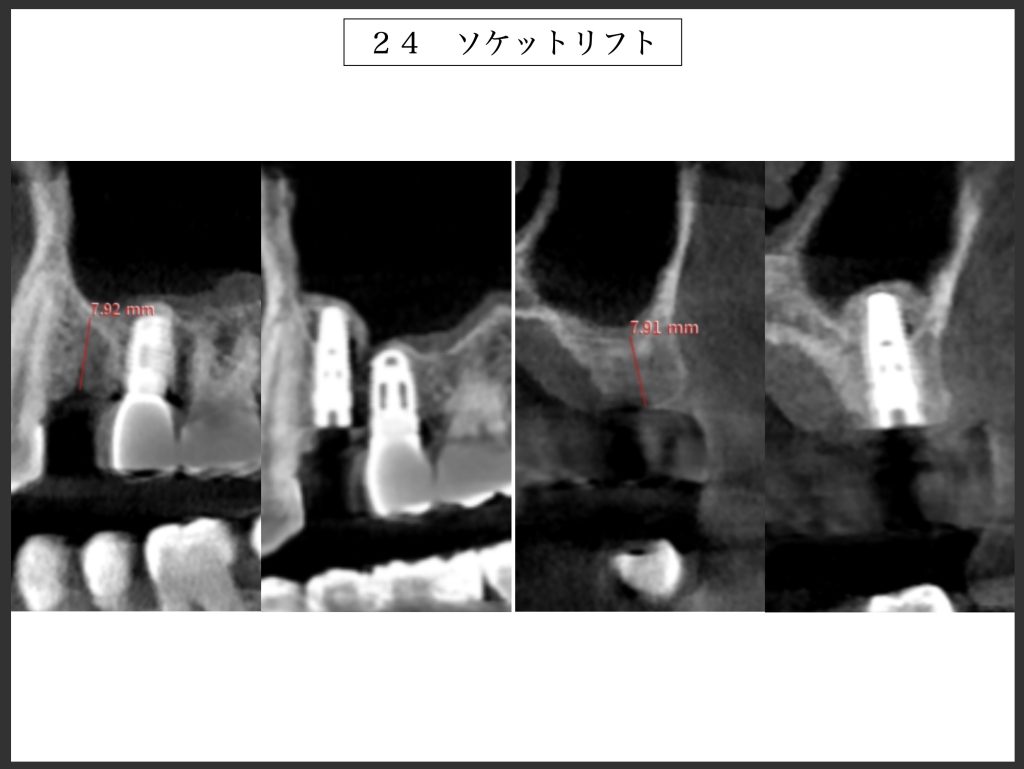

下記の症例は垂直的骨量が不足していた為、上顎洞粘膜を挙上し、同時にインプラントを埋入しました。

治療期間は4ヶ月ほどで最終補綴物を装着して終了しました。